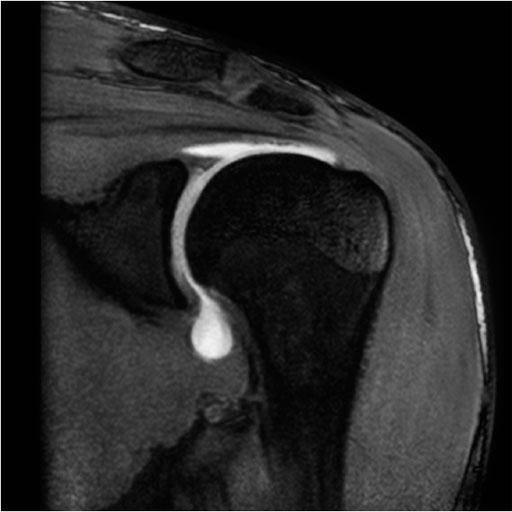

Ortho Package |

|

This package includes:

- 2D TSE protocols for PD, T1 and T2-weighted contrast

with high in-plane resolution and thin slices

- 3D MEDIC, 3D TrueFISP protocols with water excitation

for T2-weighted imaging with high in-plane resolution

and thin slices

- High resolution 3D VIBE protocol for MR arthrography

(knee, shoulder and hip)

- 3D MEDIC, 3D TrueFISP, 3D VIBE protocols with water

excitation having high isotropic resolution, optimized

for 3D post-processing

- PD SPACE with fat saturation and T2 SPACE with high

isotropic resolution optimized for 3D post-processing

- Whole spine single-step or multi-step protocols

- Excellent fat suppression in off-center positions,

e.g. in the shoulder due to high magnet homogeneity

- Dynamic TMJ and ilio-sacral joint protocol

- Susceptibility-insensitive protocols for imaging in

the presence of a prosthesis

- Multi-Echo SE sequence with up to 32 echoes for the

calculation of T2 time maps (calculation included in the

Scientific Suite)

- High resolution 3D DESS (Double Echo Steady State): T2

/ T1-weighted imaging for excellent fluid-cartilage

differentiation